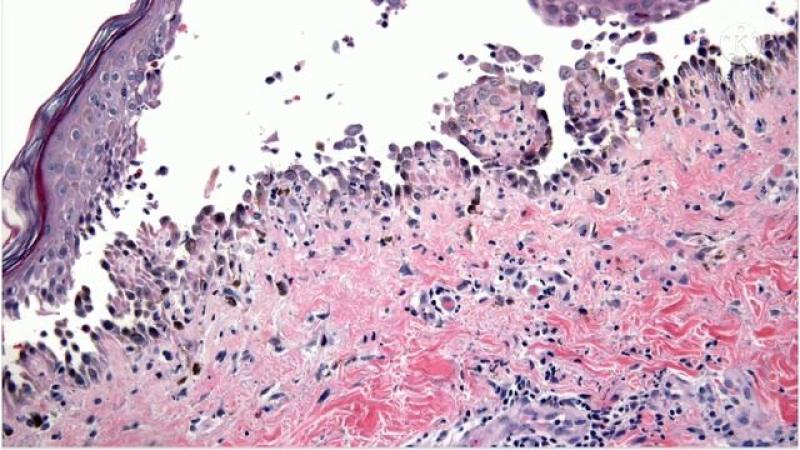

Pemphigus vulgaris (PV) is a rare, potentially life-threatening autoimmune blistering disorder primarily affecting the skin and mucous membranes. Characterized by painful blisters and erosions, PV results from autoantibodies targeting desmogleins—key proteins that maintain cell-to-cell adhesion in the epidermis. Prompt and appropriate treatment is crucial to control symptoms, prevent complications, and improve quality of life. This article delves into detailed aspects of pemphigus vulgaris treatment, highlighting current therapeutic strategies, emerging treatment modalities, and insights into market trends shaping future patient care options.